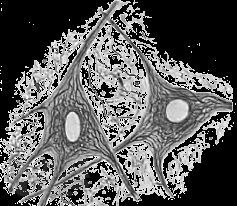

Учебное пособие предназначено для самостоятельной работы с микропрепаратами при подготовке к итоговым практическим занятиям по общему и частному курсу гистологии студентов I и II курсов лечебного и педиатрического факультетов.